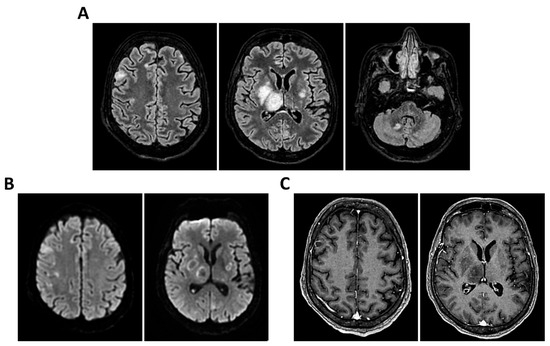

Figure 6.

MRI of patient 1 group 2. A 63-year-old man with a history of hypertension, dyslipidemia, and prior pulmonary lobectomy was admitted to the ER in a drowsy but verbally responsive state. His wife reported a recent episode of vomiting followed by loss of consciousness and tonic–clonic seizures. He was uncooperative and tremulous but afebrile, although a febrile episode had occurred in the preceding days. A lumbar puncture led to a diagnosis of Neisseria meningitidis type B meningitis. Ceftriaxone 2 g IV every 12 h was initiated. Brain CT, chest CT, and angio-CT of the epiaortic vessels showed no acute abnormalities. Due to clinical deterioration and a further seizure with hypotension, the patient was sedated, intubated, and experienced an episode of ventricular tachycardia during CT imaging, requiring IV Amiodarone. The patient was transferred to the ICU. On day 2, TCCD showed no significant flow abnormalities, with only mild asymmetry in PI (1.11 right, 1.4 left), without evidence of intracranial hypertension. (A) MRI exam with perfusion study reveal areas of altered signal intensity, hyperintense on 3D axial FLAIR sequence, (B) with diffusion restriction in axial DWI sequence, indicative of subacute inflammatory processes. These areas were scattered, the most significant is located along the subpial cortical surfaces of the left precentral and supramarginal gyri. Additionally, MRI exam demonstrates leveled material of likely inflammatory nature in both occipital horns of the lateral ventricles (A,B). (C) MRI perfusion with ASL sequence shows normal and symmetrical CBF values. Blue circles indicate the region of interest (ROI) used for quantitative CBF analysis.

Figure 8.

MRI of patient 3 group 2. A 67-year-old woman with hypertension, depressive disorder, and hypothyroidism was brought to the ER in a confused state, following three days of abdominal pain, fever, neck pain, and headache. On arrival, she was drowsy but responsive to verbal stimuli and able to follow simple commands. Total-body CT showed no cranial or abdominal pathology except for a 6 cm rectal fecaloma; lungs were clear. A lumbar puncture revealed cloudy CSF with 1100 cells/mm3. FilmArray was positive for S. pneumoniae. She was treated with Rocephin and Tazocin and transferred to our ICU. On day 2, TCCD showed no flow abnormalities, with PI values of 1.2 (right) and 1.1 (left). (A) 3D axial FLAIR sequence shows multiple hyperintense areas, without significant diffusion restriction in axial DWI sequence, localized in bilateral corona radiata and centrum semiovale and leveled material of likely inflammatory nature in both occipital horns of the lateral ventricles. (B) The perfusion study revealed normal and symmetrical CBF values. Blue and yellow circles indicate the ROI used for quantitative CBF analysis.

3.2. Group 2: TCCD and Perfusion MRI with ASL

Etiological diagnoses were heterogeneous: meningococcal meningitis (n = 1, 20%) (case 1), PML (n = 1, 20%) (case 2), Listeria monocytogenes meningoencephalitis (n = 1, 20%) (case 3), meningoencephalitis of undetermined origin (n = 1, 20%) (case 4), and pneumococcal meningitis (n = 1, 20%) (case 5). Patients underwent MRI with ASL to assess cerebral perfusion. Three patients had normal TCCD findings (PI ≤ 1.4) and symmetrical CBF (differences <15% between hemispheres). ASL imaging confirmed the absence of perfusion deficits, even in cases where FLAIR imaging revealed mild inflammatory changes. All three patients recovered their baseline neurological function at 28 days (Table 3 and Figure 6, Figure 7 and Figure 8).